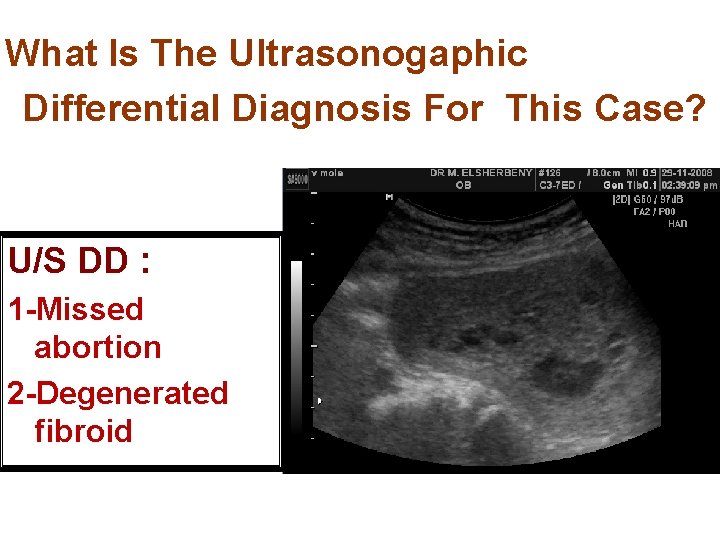

What Is The Ultrasonogaphic Differential Diagnosis For This Case? U/S DD : 1 -Missed abortion 2 -Degenerated fibroid

Differential Diagnosis: Long standing missed abortion with cystic degeneration of the placenta